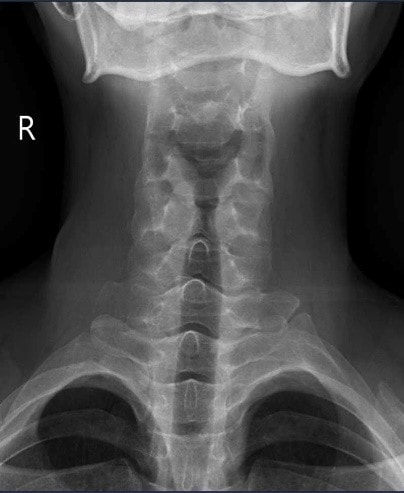

Nhiều người làm công việc văn phòng thường cho rằng, do tính chất công việc văn phòng phải ngồi nhiều, nên bị đau cổ là bình thường. Ở trường hợp này, bệnh nhân dù đã đi khám nhiều nơi, chụp X-quang cột sống cổ và dùng thuốc điều trị đau cổ nhưng tình trạng chỉ đỡ tạm thời rồi tái phát.

Tại Khoa Khám chữa bệnh theo yêu cầu và quốc tế, Bệnh viện E, ThS.BSNT Nguyễn Mạnh Quyết nhận thấy đây là trường hợp đau cột sống kiểu viêm – dấu hiệu then chốt gợi ý bệnh lý viêm khớp mạn tính. Bệnh nhân được chỉ định chụp X-quang khớp cùng chậu và làm xét nghiệm gen HLA-B27.

Kết quả cho thấy, bệnh nhân bị viêm khớp cùng chậu độ III hai bên, HLA-B27 dương tính, CRP và tốc độ lắng máu tăng. Trong khi đó, X-quang cột sống cổ vẫn chưa có biểu hiện dính khớp hay gai xương.